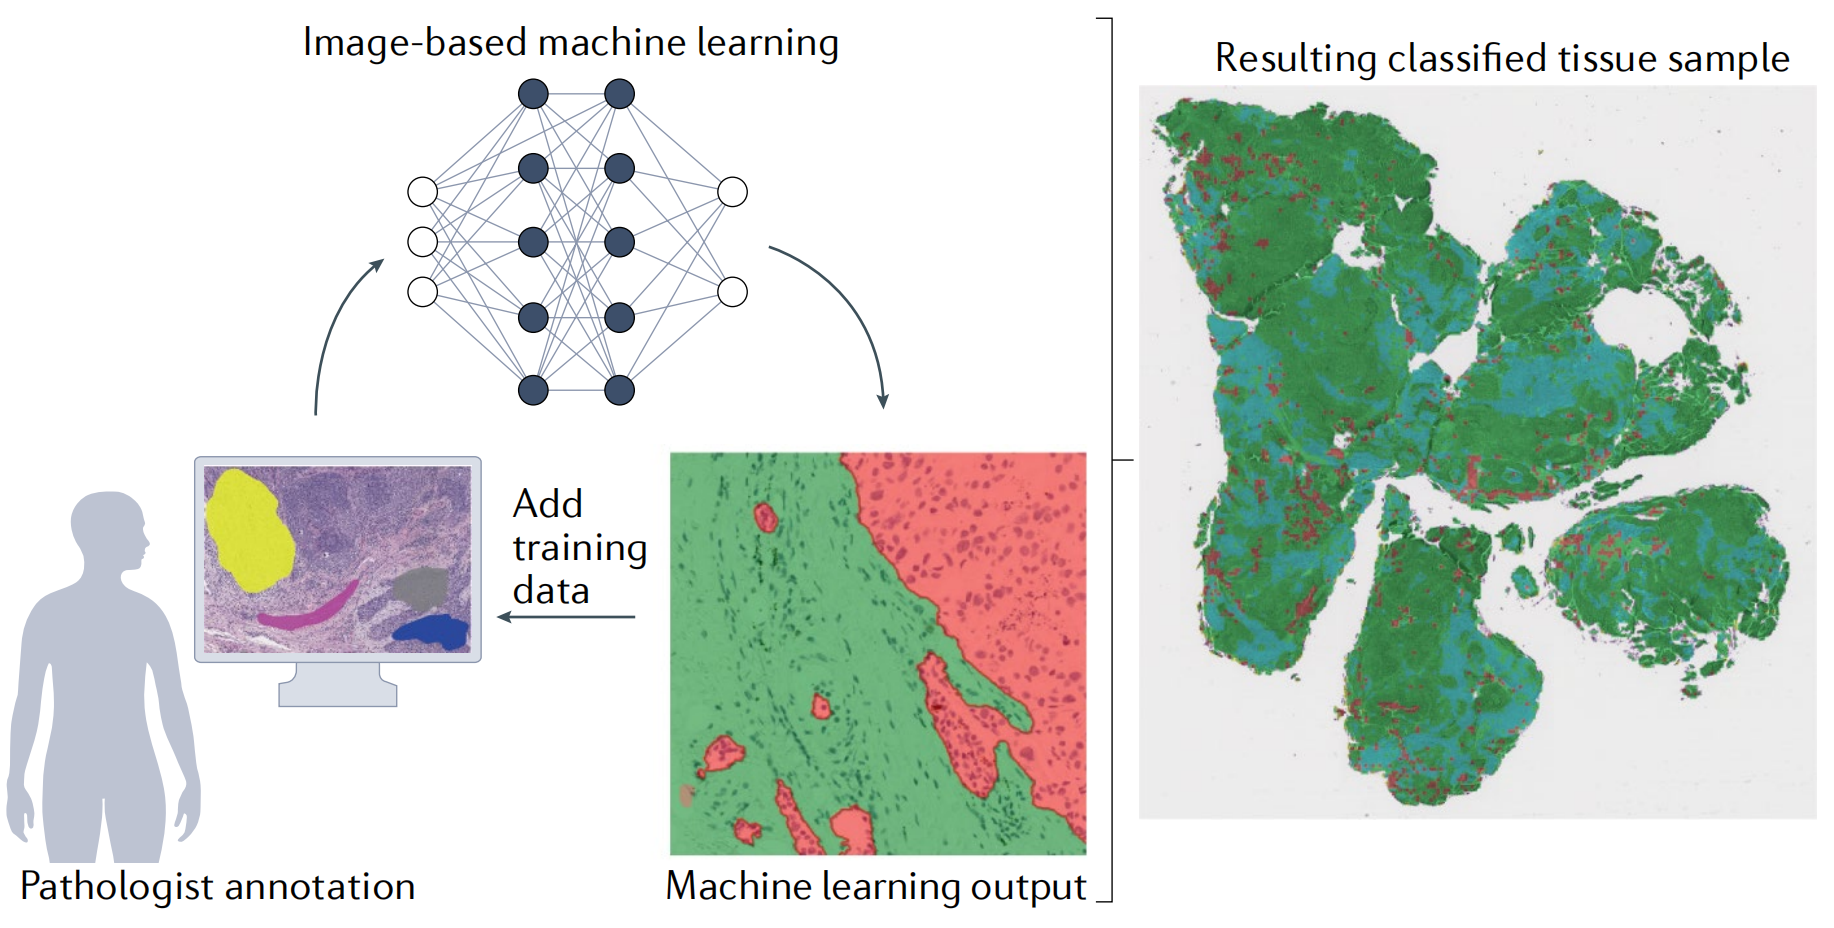

图 4 展示了主动学习(active learning)如何减轻注释的负担。主动学习是一种机器学习策略,它将人类专家的知识和机器学习模型结合起来,以更高效地利用有限的标注资源。在医学图像分析等场景中,主动学习特别有用,因为它可以减少对大量数据进行手动标注的需要,这些标注工作往往是耗时且昂贵的。

在图 4 中,主动学习的过程通常包括以下步骤:

- 专家初步标注:首先,病理学家(或专家)会手动标注一小部分训练区域,这些区域代表了不同的组织类型,例如肿瘤、基质和淋巴细胞等。

- 机器学习模型训练:接着,使用这些专家标注的数据来训练一个机器学习分类器。

- 模型评估与迭代:训练完成后,生成的标记样本会被检查,以识别分类错误的区域。然后,病理学家会针对性地增加额外的训练区域,以纠正这些错误。

- 重复迭代:这个过程会不断重复,直到分类器的准确性达到令人满意的水平。一旦模型训练完成并且准确度足够高,它就可以被应用于更广泛的样本集上。

通过这种“人类在循环中”(human-in-the-loop)的方法,主动学习可以有效地利用专家的知识和机器学习算法的自动化能力,以提高学习效率并减少所需的标注工作量。这种方法特别适用于那些获取标注数据成本高昂或时间消耗大的领域。